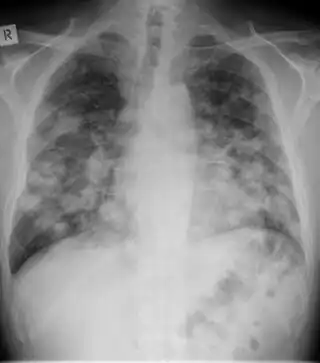

Chest X-ray: Angioinvasive aspergillosis

Chest X-ray of lungs affected by cryptococcosis

Chest X-ray of lungs affected by histoplasmosis

X-ray of cyst in pneumocystis pneumonia[17]